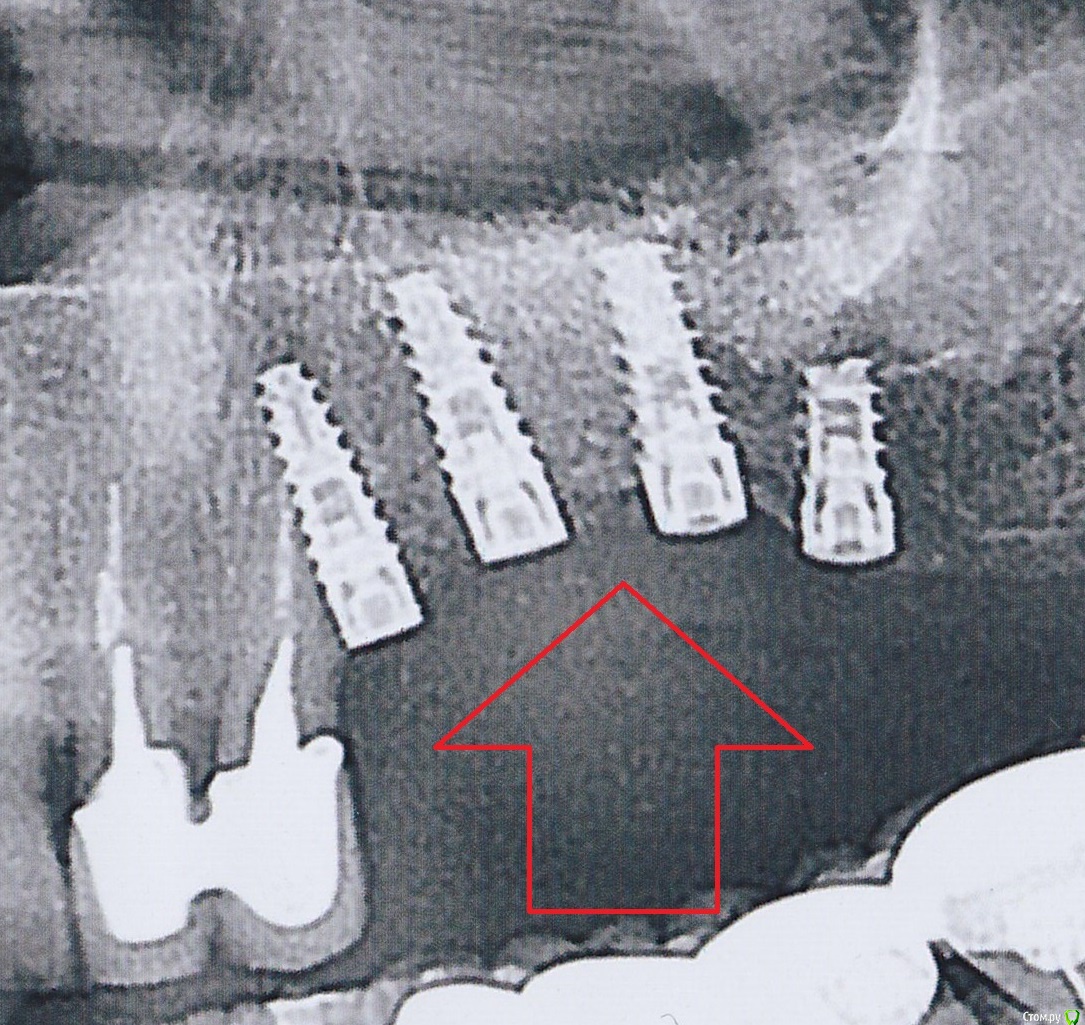

Nazim_NV86 Опубликовано 18 ноября, 2018 Поделиться Опубликовано 18 ноября, 2018 Здравствуйте. Систем имплантации сейчас сотни. Журнал операций должен быть, с датой и наклейками от имплантов. По звонку узнать не пробовали? (Похожи на альфа био spi) 1 Ссылка на комментарий

Bier Опубликовано 19 ноября, 2018 Поделиться Опубликовано 19 ноября, 2018 имплантаты похожи на израильские. Там почти у всех систем стандартно все. Alpha-Bio как вариант. Ссылка на комментарий